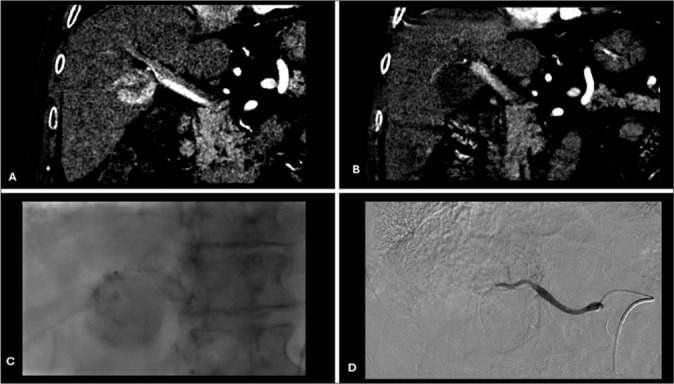

Objective: The objective of this study was to evaluate complete contrast staining (CCS) of HCC during drug-eluting bead transarterial chemoembolization (DEBTACE) first session for response prediction.

Methods: Forty-one patients with solitary HCC who underwent DEBTACE were retrospectively enrolled and divided into two groups based on contrast staining of HCC using two-dimensional (2D) fluoroscopy during the first session of DEBTACE. Both groups underwent one or two sessions of DEBTACE to achieve a complete response. Responses were evaluated using the modified Response Evaluation Criteria in Solid Tumors. A comparison of the complete response between the CCS and non-CCS groups was performed, and the prediction value was studied.

Results: CCS in 2D fluoroscopy during the first session of drug-eluting bead chemoembolization was observed in 22 (53.7%) patients. Well-defined HCC and super-selective chemoembolization were significantly associated with CCS. Complete response was observed in 54.54%, 90%, and 95.45% of CCS patient groups after the first session, second session, and cumulative sessions of TACE, respectively. Complete responses were 10.52%, 29.41%, and 36.84% in the non-CCS group after the first, second, and cumulative sessions of TACE, respectively.

Conclusion: CCS of HCC using 2D fluoroscopy during DEBTACE is a predictor of a favorable response after two sessions of treatment.